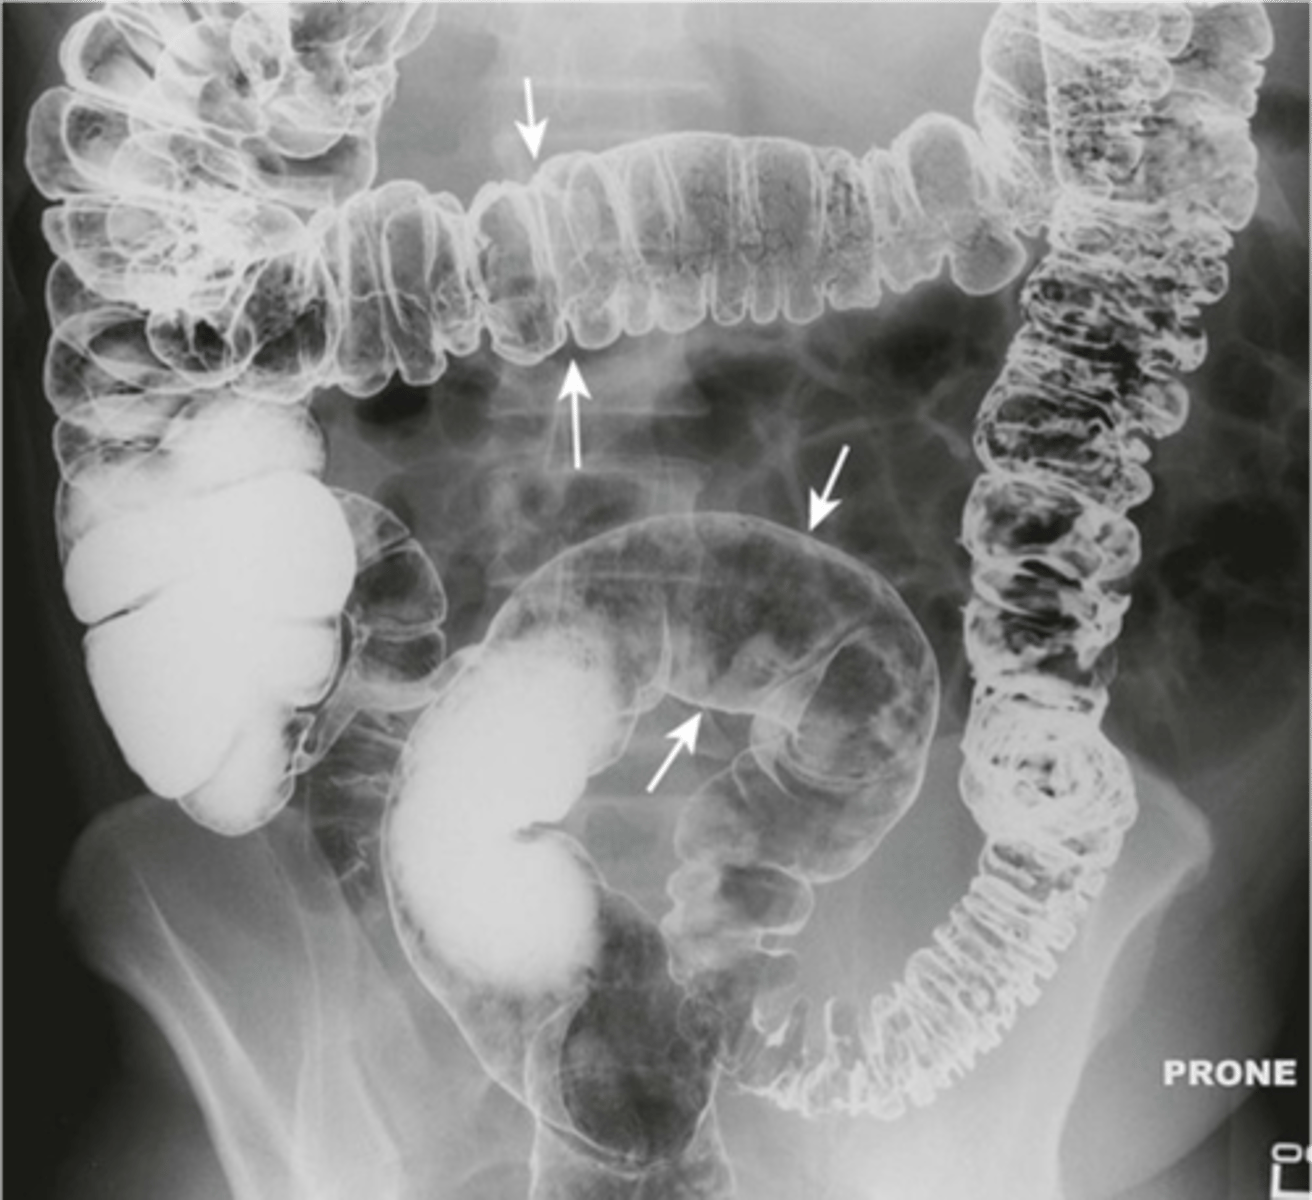

Normal colonic distension (barium enema study)

shows large bowel on barium swallow with follow through

Large bowel Haustra

Large bowel haustra (pic 2)